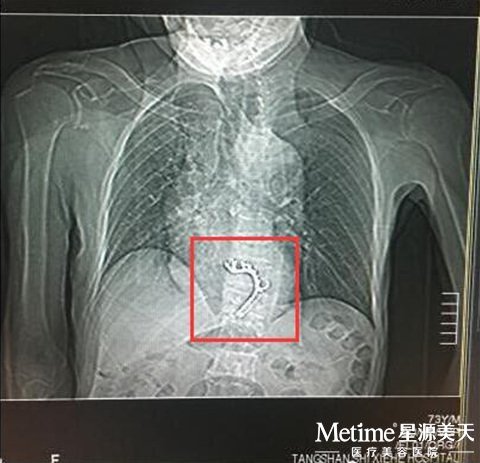

王老先生的CT片显示 体内有假牙托异物

老人因为自身疾病以及数日不能正常进食等原因,已经出现了胸痛,精神萎靡、心动过速等症状。家人急忙把老人送到了医院,经过耳鼻喉科、消化内科专家的联合会诊后,采取经胃镜试取异物手术。镜下发现,假牙托的金属卡环牢牢卡在了食道下段一动不动,而周围的食道软组织由于假牙托的压迫出现了水肿、溃疡情况。如果假牙不能及时取出,锋利的金属卡环很有可能刺穿已经溃烂的食道,一旦刺入旁边的大动脉里即可造成大出血,后果不堪设想。老人被送到医院后,医生决定为老人采取开胸取异物。开胸后发现食道下段有一处质硬的异物,已经出现严重水肿,食道组织已经严重破坏。经过医生巧妙地把食道拉向对侧组织,远离开主动脉,逐层分离后,终于成功切下病变部位,病情化险为夷,目前王老先生正在逐渐康复之中。